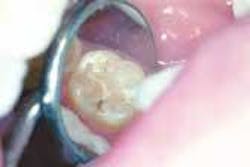

Since the introduction of fluoridation, outwardly detectable decay has been dramatically reduced. Because of the strengthening that fluoride creates in the outer layer of tooth enamel, the pattern of decay has changed. Rather than large areas of a tooth surface succumbing to the attack of plaque acid, decay now appears as small discreet areas, often undetectable to the dental probe, yet visible as a color change inside the tooth under magnification. Dentists have observed this change, and have continued to develop a science based on prevention and protection and the continuing miniaturization of all treatment procedures. New filling and restorative materials and techniques also have been developed. The new techniques require early and aggressive investigation of stains, the targeted removal of unsound tooth structure vs. the indiscriminate removal of sound tooth structure, and bonded restorations rather than traditional "drill, fill, and bill" approaches.

Because the failure rate among sealants is so high, we meticulously examine each sealant our patients have. The examination includes placing a caries-detection dye on the sealants using high resolution video-imaging. If a sealant is leaking, good magnification will show the tint of the dye under the sealant. A failed sealant is then easily removed, utilizing the parallel water stream technique. The operative field is flooded with water, while air abrasion is simultaneously used to selectively remove the sealant.